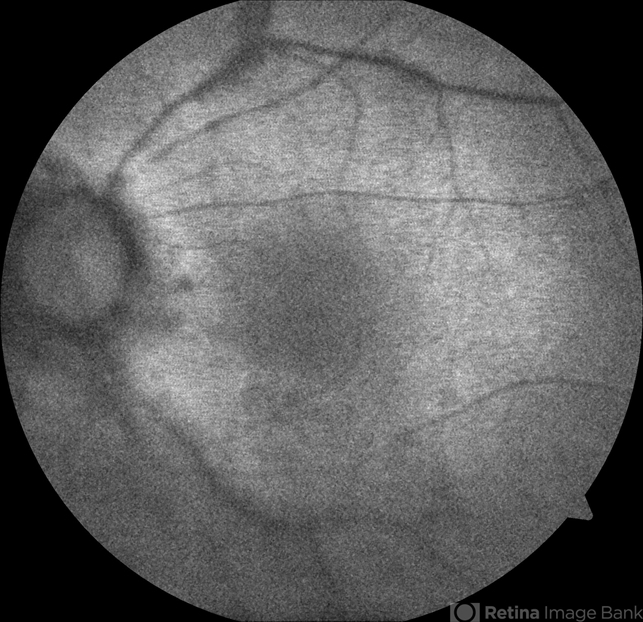

- birdshot retinochoroidopathy, birdshot, birdshot chorioretinopathy

- 64-year-old Puerto Rican woman consulted due to the presence of 1+ vitreous cells. The fundus examination revealed orange to yellow lesions dispersing from the disk. Work-up revealed she was HLA-A29 positive and the suspected diagnosis of Birdshot Chorioretinopathy was made. Chest X-Ray, FTA-Abs and RPR were negative.